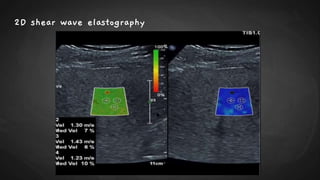

2D shear wave elastography

● SWE can be performed using acoustic radiation force impulse (ARFI) technology either in a

1. Point–shear wave elastography, (p-SWE) small region of interest (ROI) or

2. Two-dimensional shear wave elastography [2D-SWE] over a larger field of view using

color-coding to visually display the stiffness values